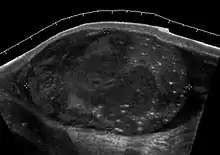

Teratoma Although teratoma is the second most common testicular tumor in children, it affects all age groups. Mature teratoma in children is often benign, but teratoma in adults, regardless of age, should be considered malignant. Teratomas are composed of all three germ cell layers, i.e. endoderm, mesoderm and ectoderm. At ultrasound, teratomas generally form well-circumscribed complex masses. Echogenic foci representing calcification, cartilage, immature bone and fibrosis are commonly seen [Fig. 5]. Cysts are also a common feature and depending on the contents of the cysts i.e. serous, mucoid or keratinous fluid, it may present as anechoic or complex structure [Fig. 6].

Fig. 5. Teratoma. A plaque-like calcification with acoustic shadow is seen in the testis.